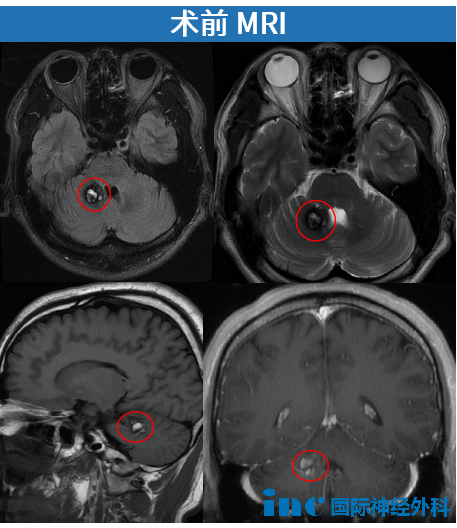

術(shù)前影像

血管瘤位于小腦偏腹側(cè),位置較深(距離枕骨遠(yuǎn)),對手術(shù)入路要求較高。雖然體積不大,但埋于正常小腦皮質(zhì)下方,術(shù)中難以確認(rèn)造瘺位置。通過幕下小腦上這一自然解剖間隙雖可最大程度降低小腦實質(zhì)損傷,但手術(shù)操作空間狹小,對術(shù)者技術(shù)要求極高。